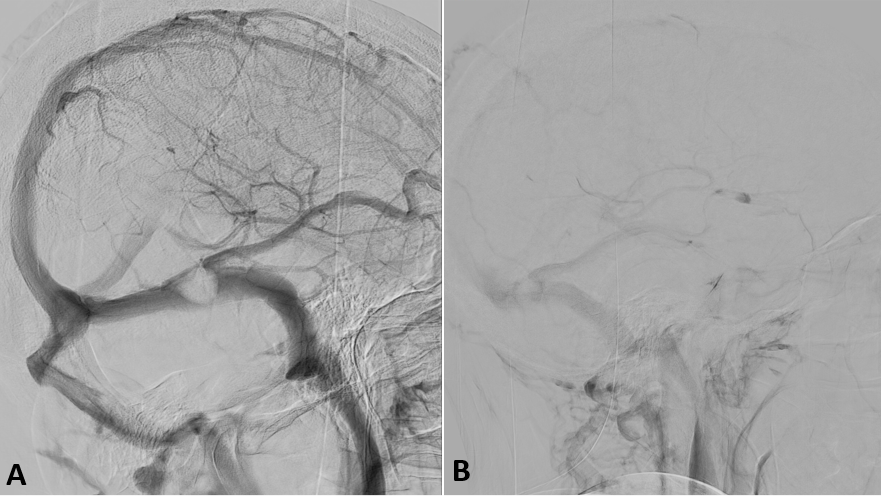

He was referred to the interventional neuroradiology unit and underwent a diagnostic arteriography that showed stenosis of the left transverse sinus at the level of the vein of Labbé drainage, in which a small diverticulum with slow flow was observed (Figure 2). No evidence of dural or pial arteriovenous fistula, arteriovenous malformation, aneurysms or signs of vasculitis were found. Given the clinical picture and radiological findings, endovascular treatment was scheduled.

A selective venous catheterization with stent placement in the left transverse sinus was planned. Systemic anticoagulation with sodium heparin and antiaggregation with acetylsalicylic acid was administered prior to the procedure, as well as 12 mg of endovenous dexamethasone. After obtaining venous access through the left jugular vein, a guide catheter was placed in the left transverse sinus. Angiographic series and pressure measurements were performed, documenting a gradient pressure greater than 8 mmHg and significant hemodynamic stenosis at the level of the middle third of the left transverse sinus in the region of the vein of Labbé drainage, visualizing a delay in angiographic times at the level of the lateral sinus, vein of Labbé, as well as tributaries and secondary moderate congestion of the deep venous system. A 9x40 mm Wallstent (Boston Scientific, USA) was placed in the left transverse sinus covering the area of stenosis. Improvement of venous drainage resulting in disappearance of contrast retention was observed in the initial series (Figure 3).